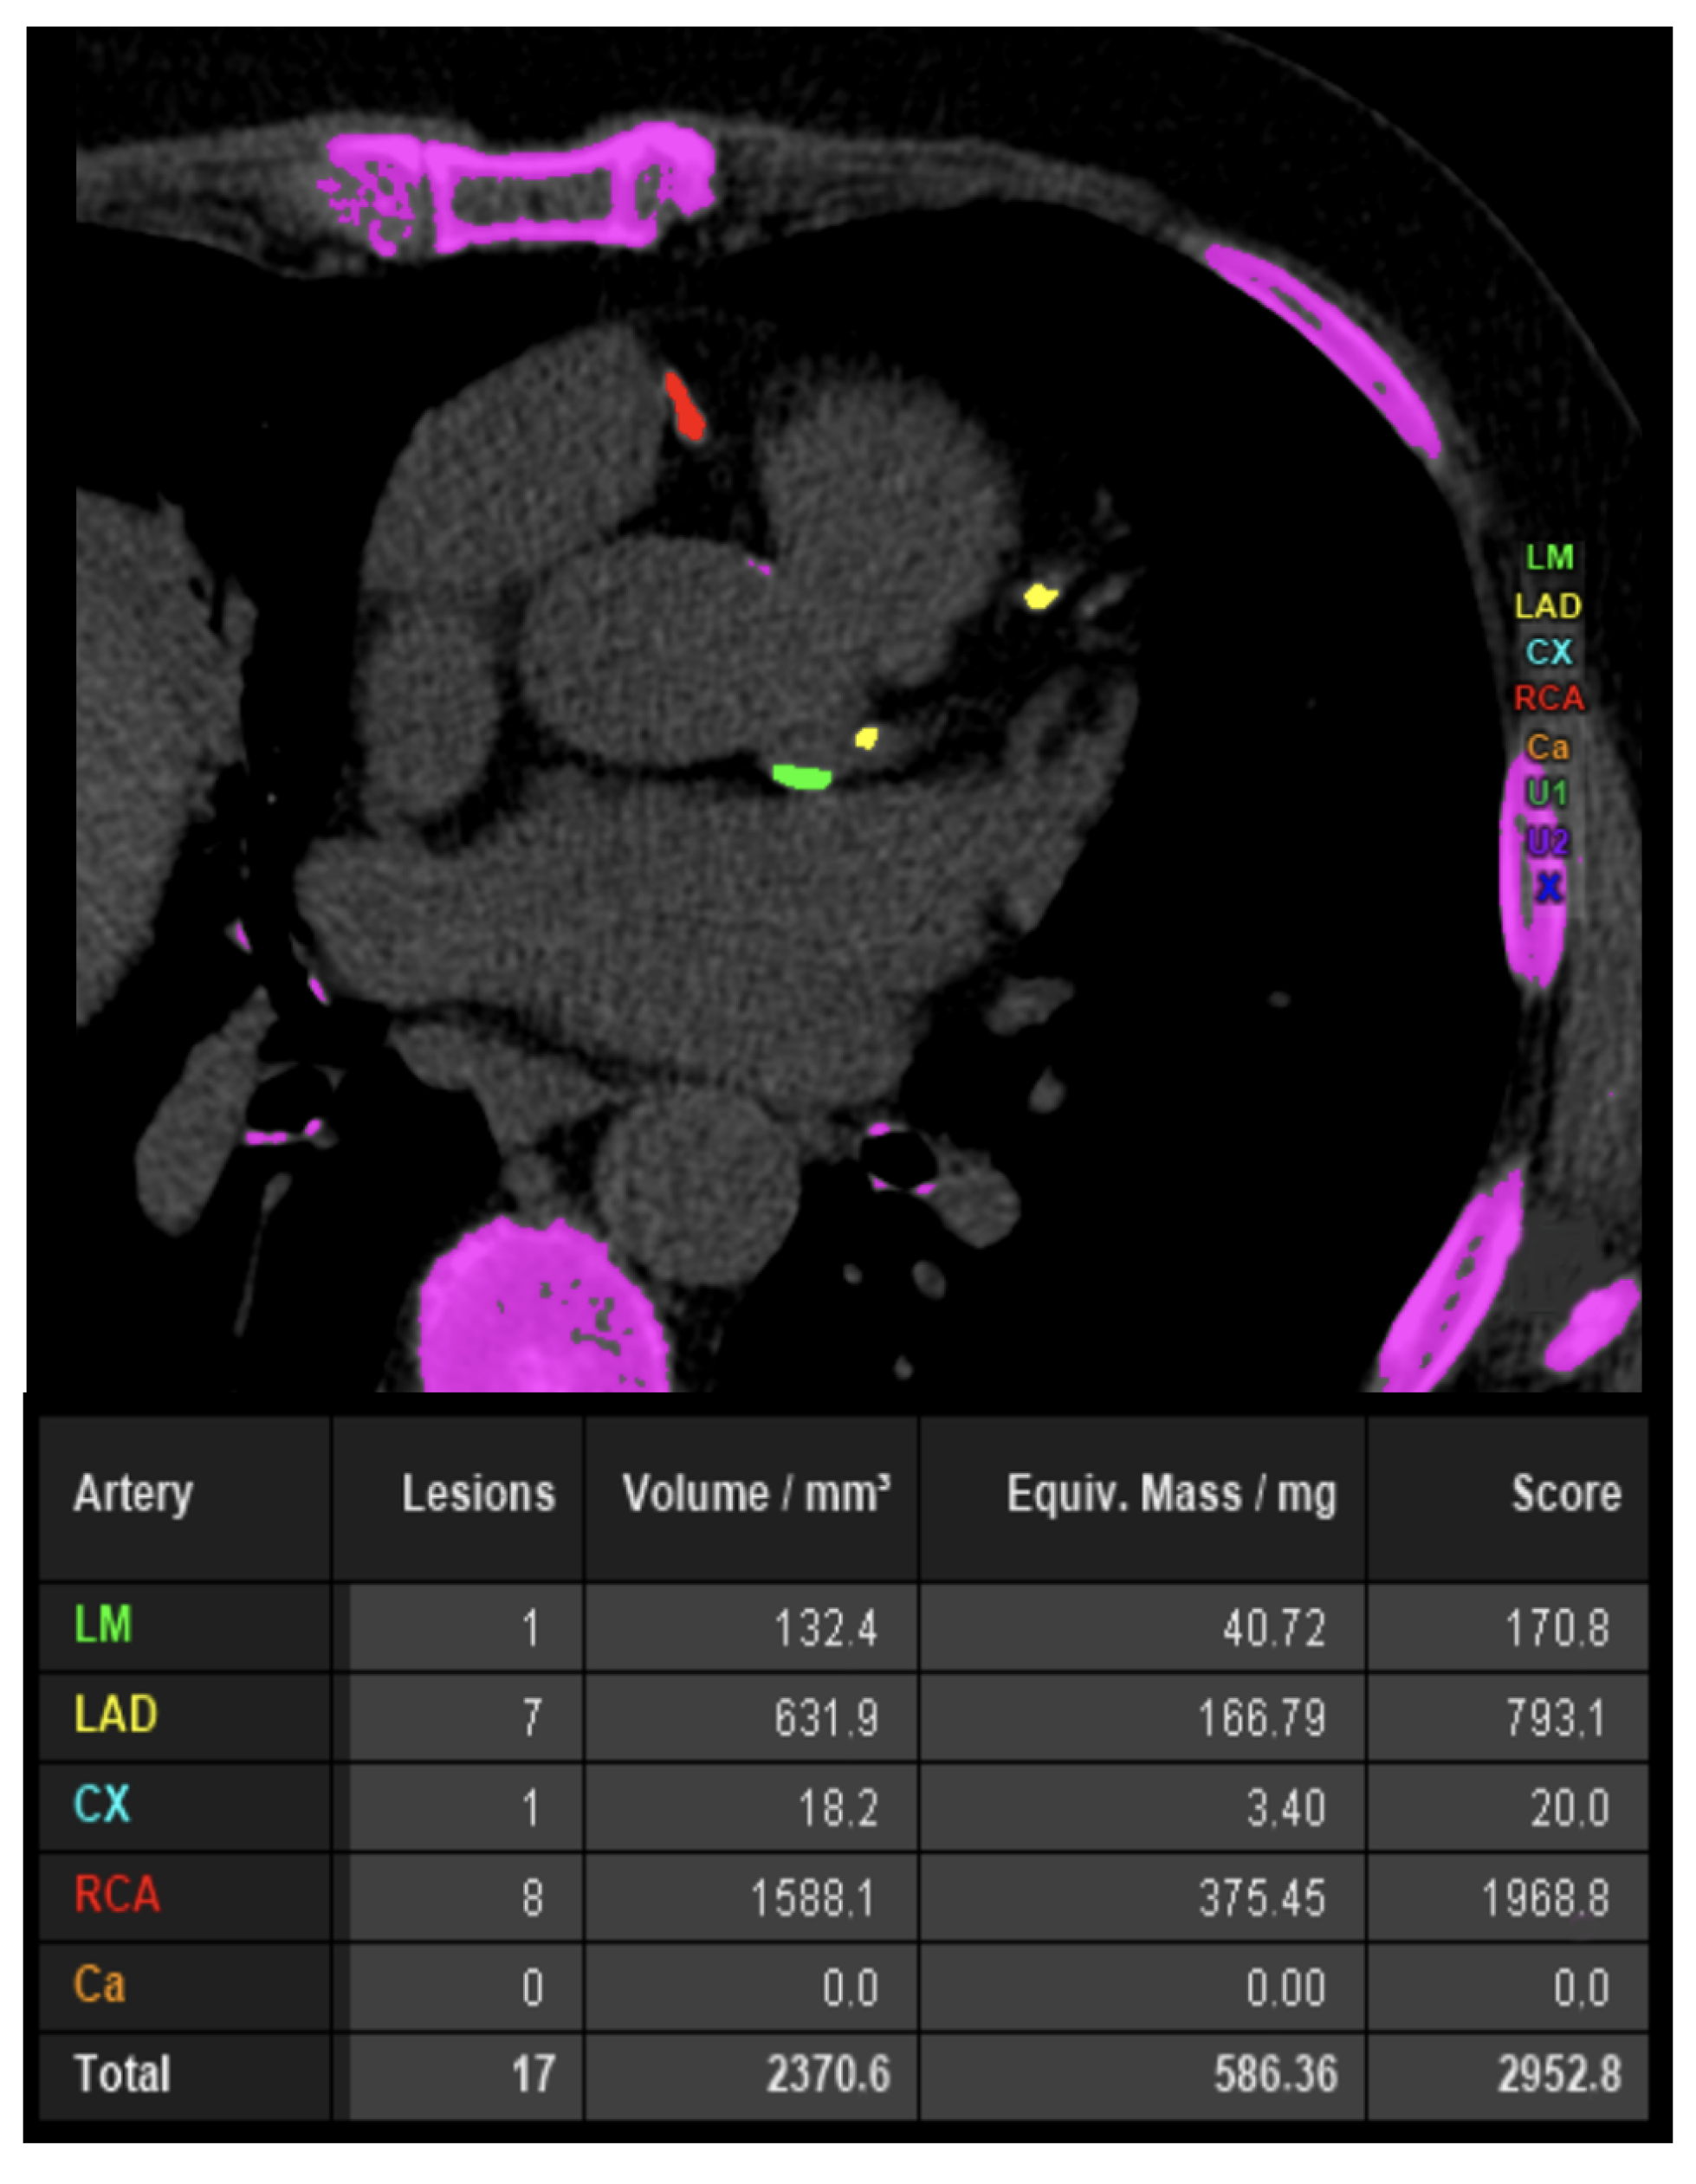

7. Coronary Artery Calcium Score